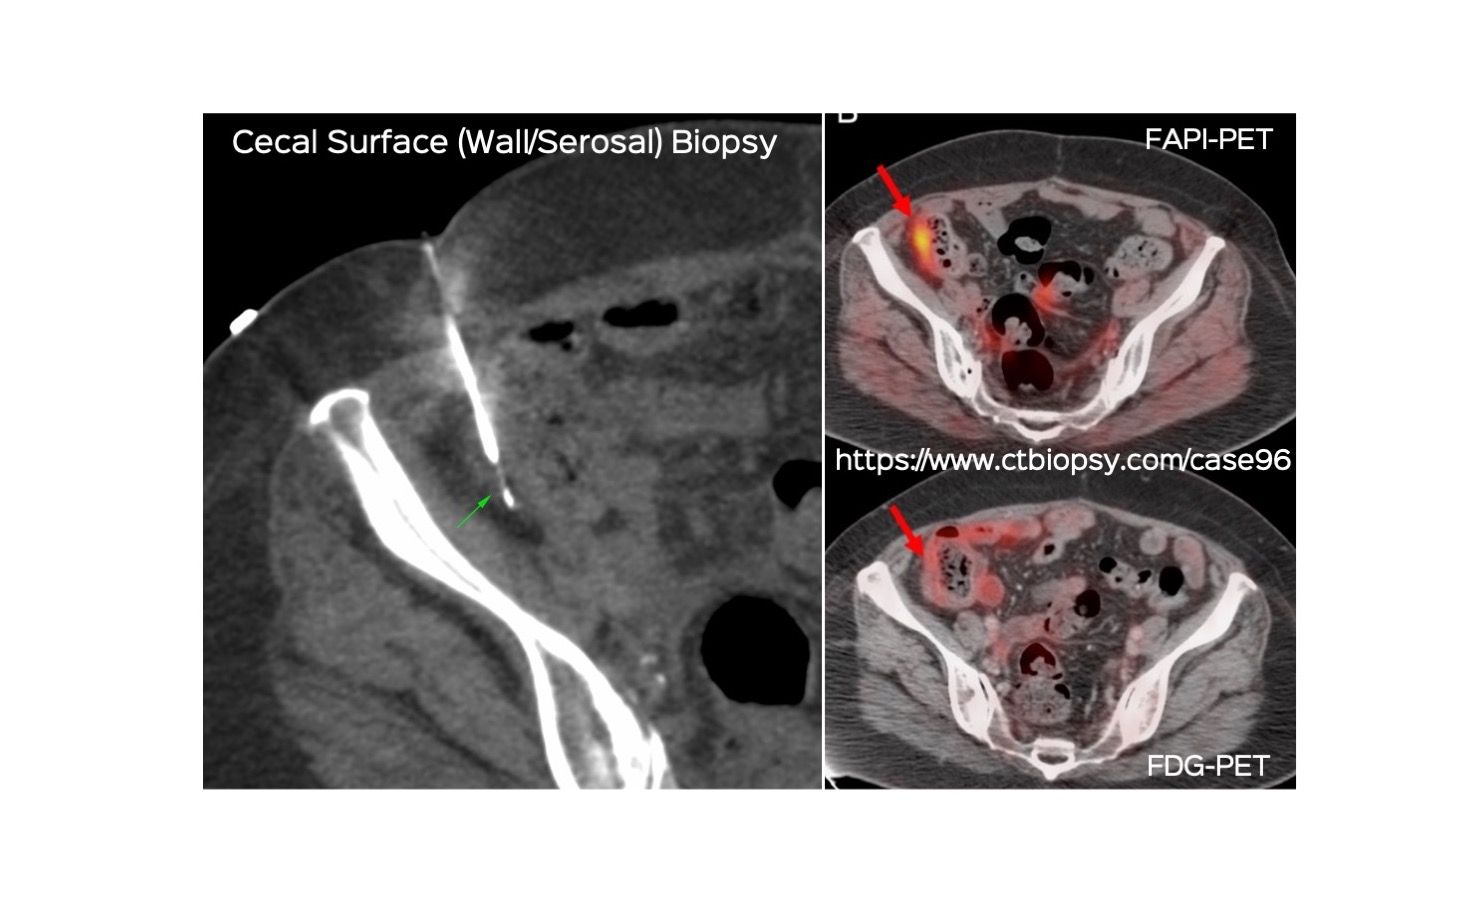

Case 96: Cecal Surface (Serosal/Wall) Biopsy (…and the value of FAPI-PET)

Bhavin Jankharia - 02 July 2022